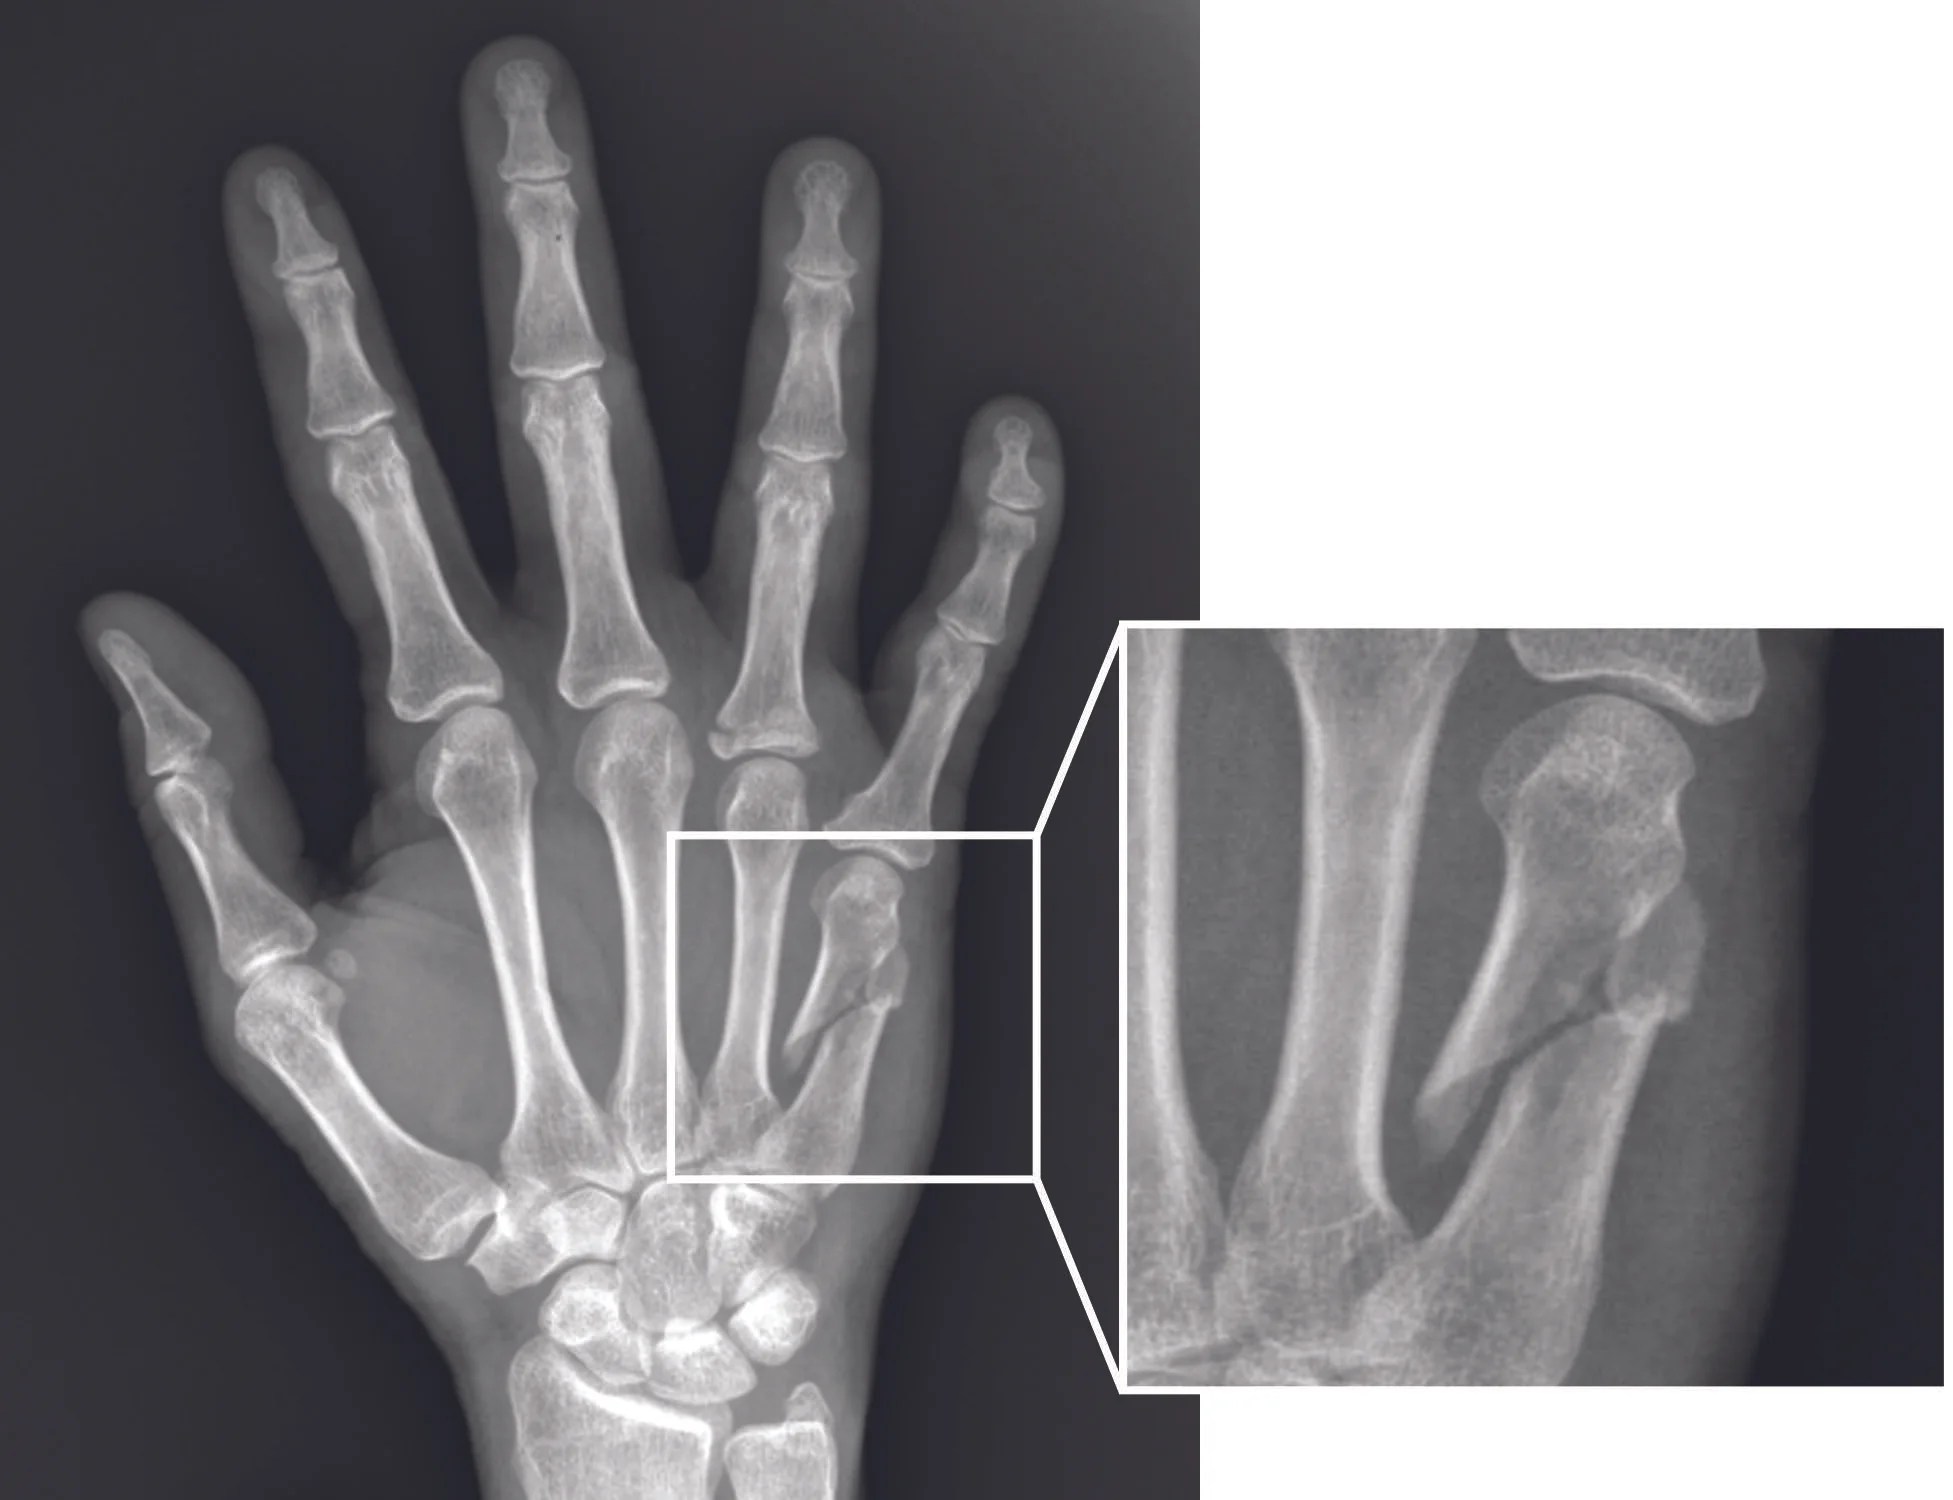

El sistema musculoesquelético brinda soporte, estabilidad y movilidad. Cuando existe fragilidad ósea o deterioro articular, el riesgo de traumatismos aumenta considerablemente. Un traumatólogo CDMX realiza estudios clínicos y de imagen como radiografías o densitometría ósea para valorar la salud ósea.

El diagnóstico temprano reduce la probabilidad de fracturas de cadera, muñeca o columna, que suelen estar asociadas a caídas en personas mayores.